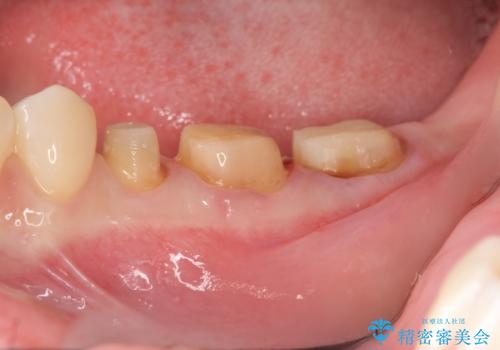

- 左下の歯が虫歯により崩壊し、歯ぐきからの出血も毎回歯ブラシを行う際に出ることから治療を求めて来院されました。

現在装着されているクラウンを除去したところ、クラウンマージンが歯肉縁下となり歯ぐきの炎症が認められたため再度オールセラミッククラウンを製作する前に歯周外科手術を行い歯ぐきの状態を改善しました。